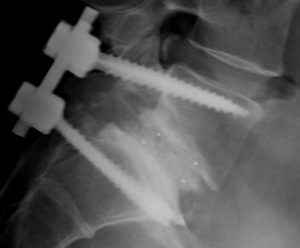

После установления костной пластики позвонки фиксируются между собой, чтобы помочь процессу слияния. В качестве фиксаторов могут быть использованы скобки, пластины, винты и стержни, чтобы обеспечить неподвижное соединение позвоночника до образования прочного их соединения. Это называется внутренней фиксацией, она значительно ускоряет срок выздоровления и дает возможность пациентам начать движение как можно раньше.